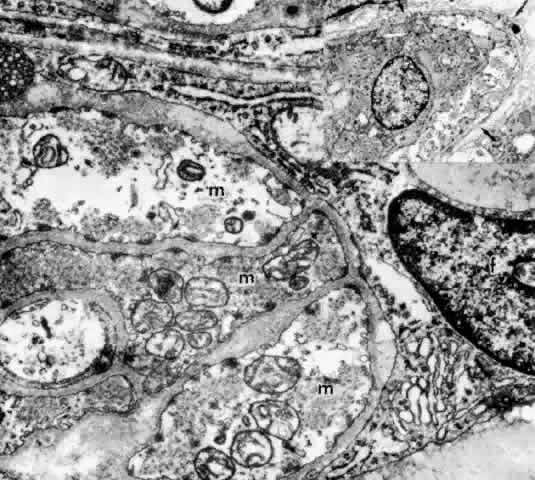

While the ultrastructure of the PE is similar in most areas of the ciliary body, that of the NPE shows noticeable regional differences that appear to be of functional importance. These differences have been studied more extensively in the monkey than in the human but are similar in both species.2,16–26 The pars plicata, and particularly its anterior portion, appears to be the predominant site of aqueous formation and has many special characteristics of this secretory function. The NPE here has marked cytoplasmic infolding at its base and redundant interdigitations at its basolateral margins, greatly increasing the area of the cell surface facing the posterior chamber (Fig. 15, Inset A). These cell membranes and, to a lesser degree, those of the pigmented epithelium contain the enzyme complex Na+ /K+ -ATPase, evidence of anenergy-dependent active transport system.27 The presence of the enzyme carbonic anhydrase in the NPE cells of the pars plicata of all species studied is further evidence of fluid-pumping activity.28 In the moderately electron-lucent cytoplasm of the anterior NPE particularly, there are large numbers of mitochondria near the base of the cell and rough endoplasmic reticulum (RER) in single cisternae or parallel stacks near the nucleus, where Golgi complexes are also common22 (Fig. 16). The mitochondria are of importance in providing energy for transport, and the RER for processing of new protein. Clusters of free ribosomes and occasional cilia are found in all areas. With aging, unusual whorled formations of RER are described near the cell base in the pars plicata, along with lipid droplets and lysosomal residual bodies.17,22

Fig. 16. Ciliary epithelium in the anterior pars plicata of a 19-year-old. Posterior chamber surface (PC) of the nonpigmented epithelium (NPE) has a sawtooth pattern seen irregularly throughout this layer with aging. Mitochondria (m) are large, plentiful, and show artifactual hydropic change. Rough endoplasmic reticulum is present below the nuclei (asterisk). Note that the apices of the pigmented epithelial cells (PE) are conical, with prolongations of NPE between them. (X 8320)